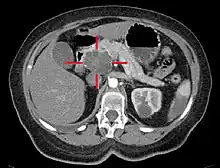

Medical imaging techniques, such as computed tomography (CT scan) and endoscopic ultrasound (EUS) are used both to confirm the diagnosis and to help decide whether the tumor can be surgically removed (its "resectability").[12] On contrast CT scan, pancreatic cancer typically shows a gradually increasing radiocontrast uptake, rather than a fast washout as seen in a normal pancreas or a delayed washout as seen in chronic pancreatitis.[50] Magnetic resonance imaging and positron emission tomography may also be used,[11] and magnetic resonance cholangiopancreatography may be useful in some cases.[30] Abdominal ultrasound is less sensitive and will miss small tumors, but can identify cancers that have spread to the liver and build-up of fluid in the peritoneal cavity (ascites).[12] It may be used for a quick and cheap first examination before other techniques.[51]